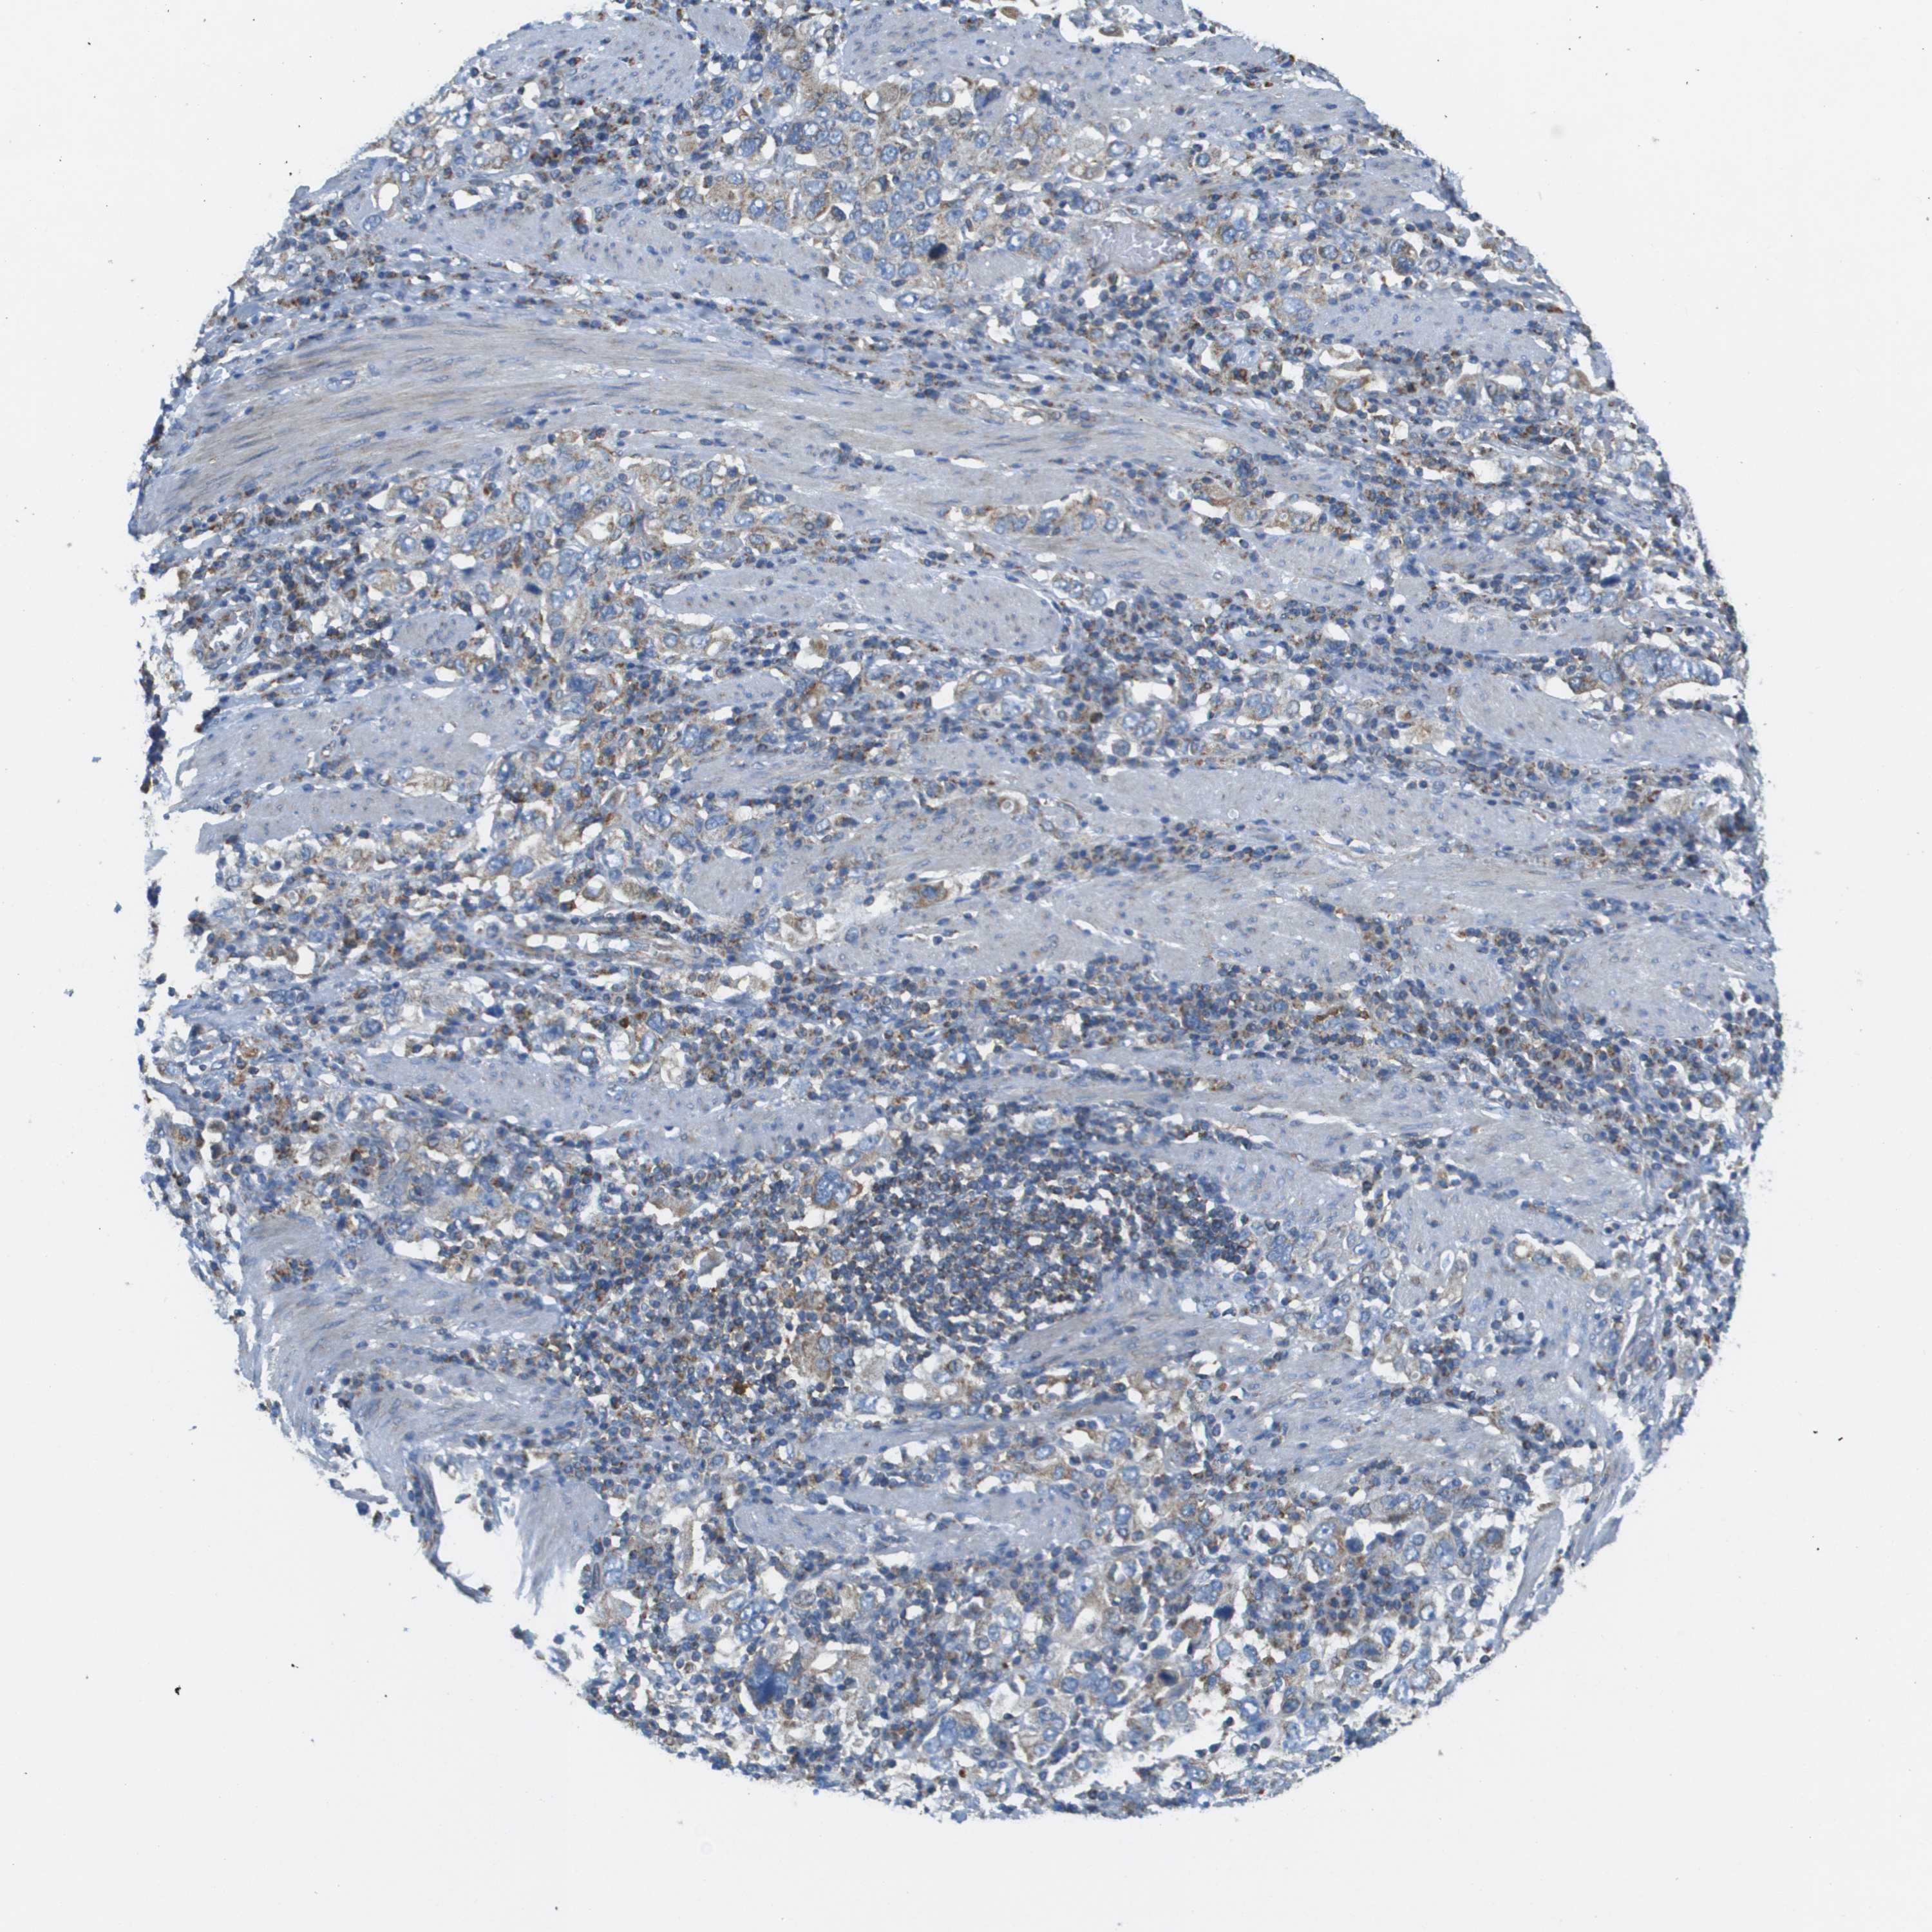

STOMACH CANCER - Protein expressioni

A mouse-over function shows sample information and annotation data. Click on an image to view it in a full screen mode. Samples can be filtered based on level of antibody staining by selecting one or several of the following categories: high, medium, low and not detected. The assay and annotation is described here.

Antibody stainingi

Antibody staining in the annotated cell types in the current human tissue is reported as not detected, low, medium, or high, based on conventional immunohistochemistry profiling in selected tissues. This score is based on the combination of the staining intensity and fraction of stained cells.

Each image is clickable and will lead to virtual microscopy that enables deeper exploration of all samples and also displays staining intensity scores, fraction scores and subcellular localization as well as patient and tissue information for each sample.

Antibody HPA017160

Staining

High

Medium

Low

Not detected

Intensity

Strong

Moderate

Weak

Negative

Quantity

>75%

75%-25%

<25%

None

Location

Nuclear

Cytoplasmic/membranous

Cytoplasmic/membranous,nuclear

Adenocarcinoma, NOS